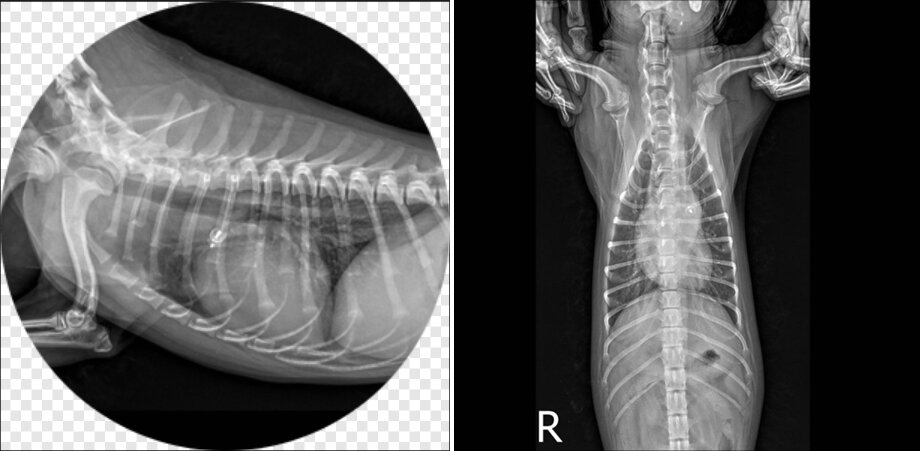

PDA 플러그 시술이 완료된 모습(SD동물의료센터 제공) ⓒ 뉴스1